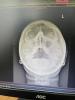

Рентген пазух: отёк или жидкость?

А есть кто разбирается в рентген снимке пазух ? Просто несколько врачей разошлись во мнении , фото в коментах , вопрос больше по лобным пазухам , есть ли отек ? Или жидкость ?

В лобных нет отека, просто лаборант перезапрокинул голову.

Гайморит и фронтит лечатся одинаково. Все пазухи связаны с носом. Так что если гайморит , то и фронтит скорее всего.

Делайте в след раз кт, там все точно будет видно. Но лечение от этого не изменится!!!!

Да я сейчас от другого Лора вышла сказала фронтита нет , назначила другое лечение 😂блин сходила за мнением другим странно что болел лоб